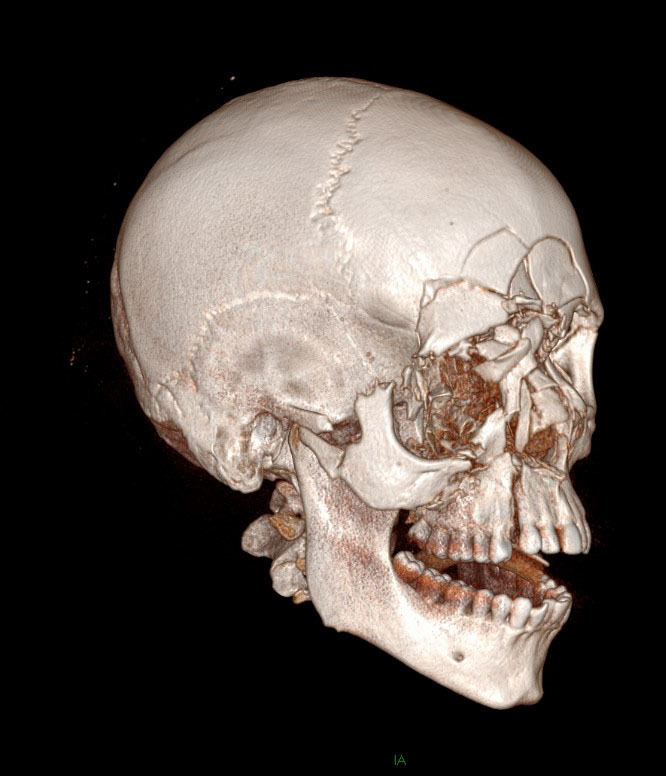

Question 4 - Il n’y a pas d’urgences neurochirurgicales sur le scanner (pas d’hématome intracrânien ni de brèche ostéoméningée). Voici les clichés de reconstruction 3D. Figure 2Figure 3Figure 4

Il y a une fracture complexe des OPN, qui s’intègre d’ailleurs dans une fracture CNEMFO

On retrouve une fracture verticale de l’hémi-maxillaire droit

Le zygoma droit est complètement détaché du bloc osseux facial. Le gauche est normal

Il n’y a aucun trait de fracture sur la mandibule

Il y a une fracture centro-faciale importante

Il y a plusieurs fractures faciales chez ce patient. On retrouve en premier lieu une fracture du CNEMFO, ainsi que deux autres fractures : fracture du zygoma droit et fracture verticale du maxillaire droit.

Rappel sur le CNEMFO : une fracture du complexe naso-éthmoïdo-maxillo-fronto-orbitaire fait suite à un choc de haute vélocité centro-facial. Le point d’impact pourrait correspondre à une fracture des os propres du nez (OPN), mais l’importance du choc entraîne un écrasement complet de la pyramide nasale et une fracture des os environnants : l’os frontal vers le haut, l’orbite (paroi médiale et plancher), la branche montante du maxillaire, et l’os éthmoïdal en arrière. Lorsque la fracture est isolée, il n’y a pas d’atteinte du zygoma.

Typiquement, la reconstruction chirurgicale n’est pas urgente et est différée de quelques jours après une diminution de l’œdème. Il s’agit de réaliser une ostéosynthèse des fractures et de projeter la pyramide nasale pour fermer le télécanthus. Figure 5